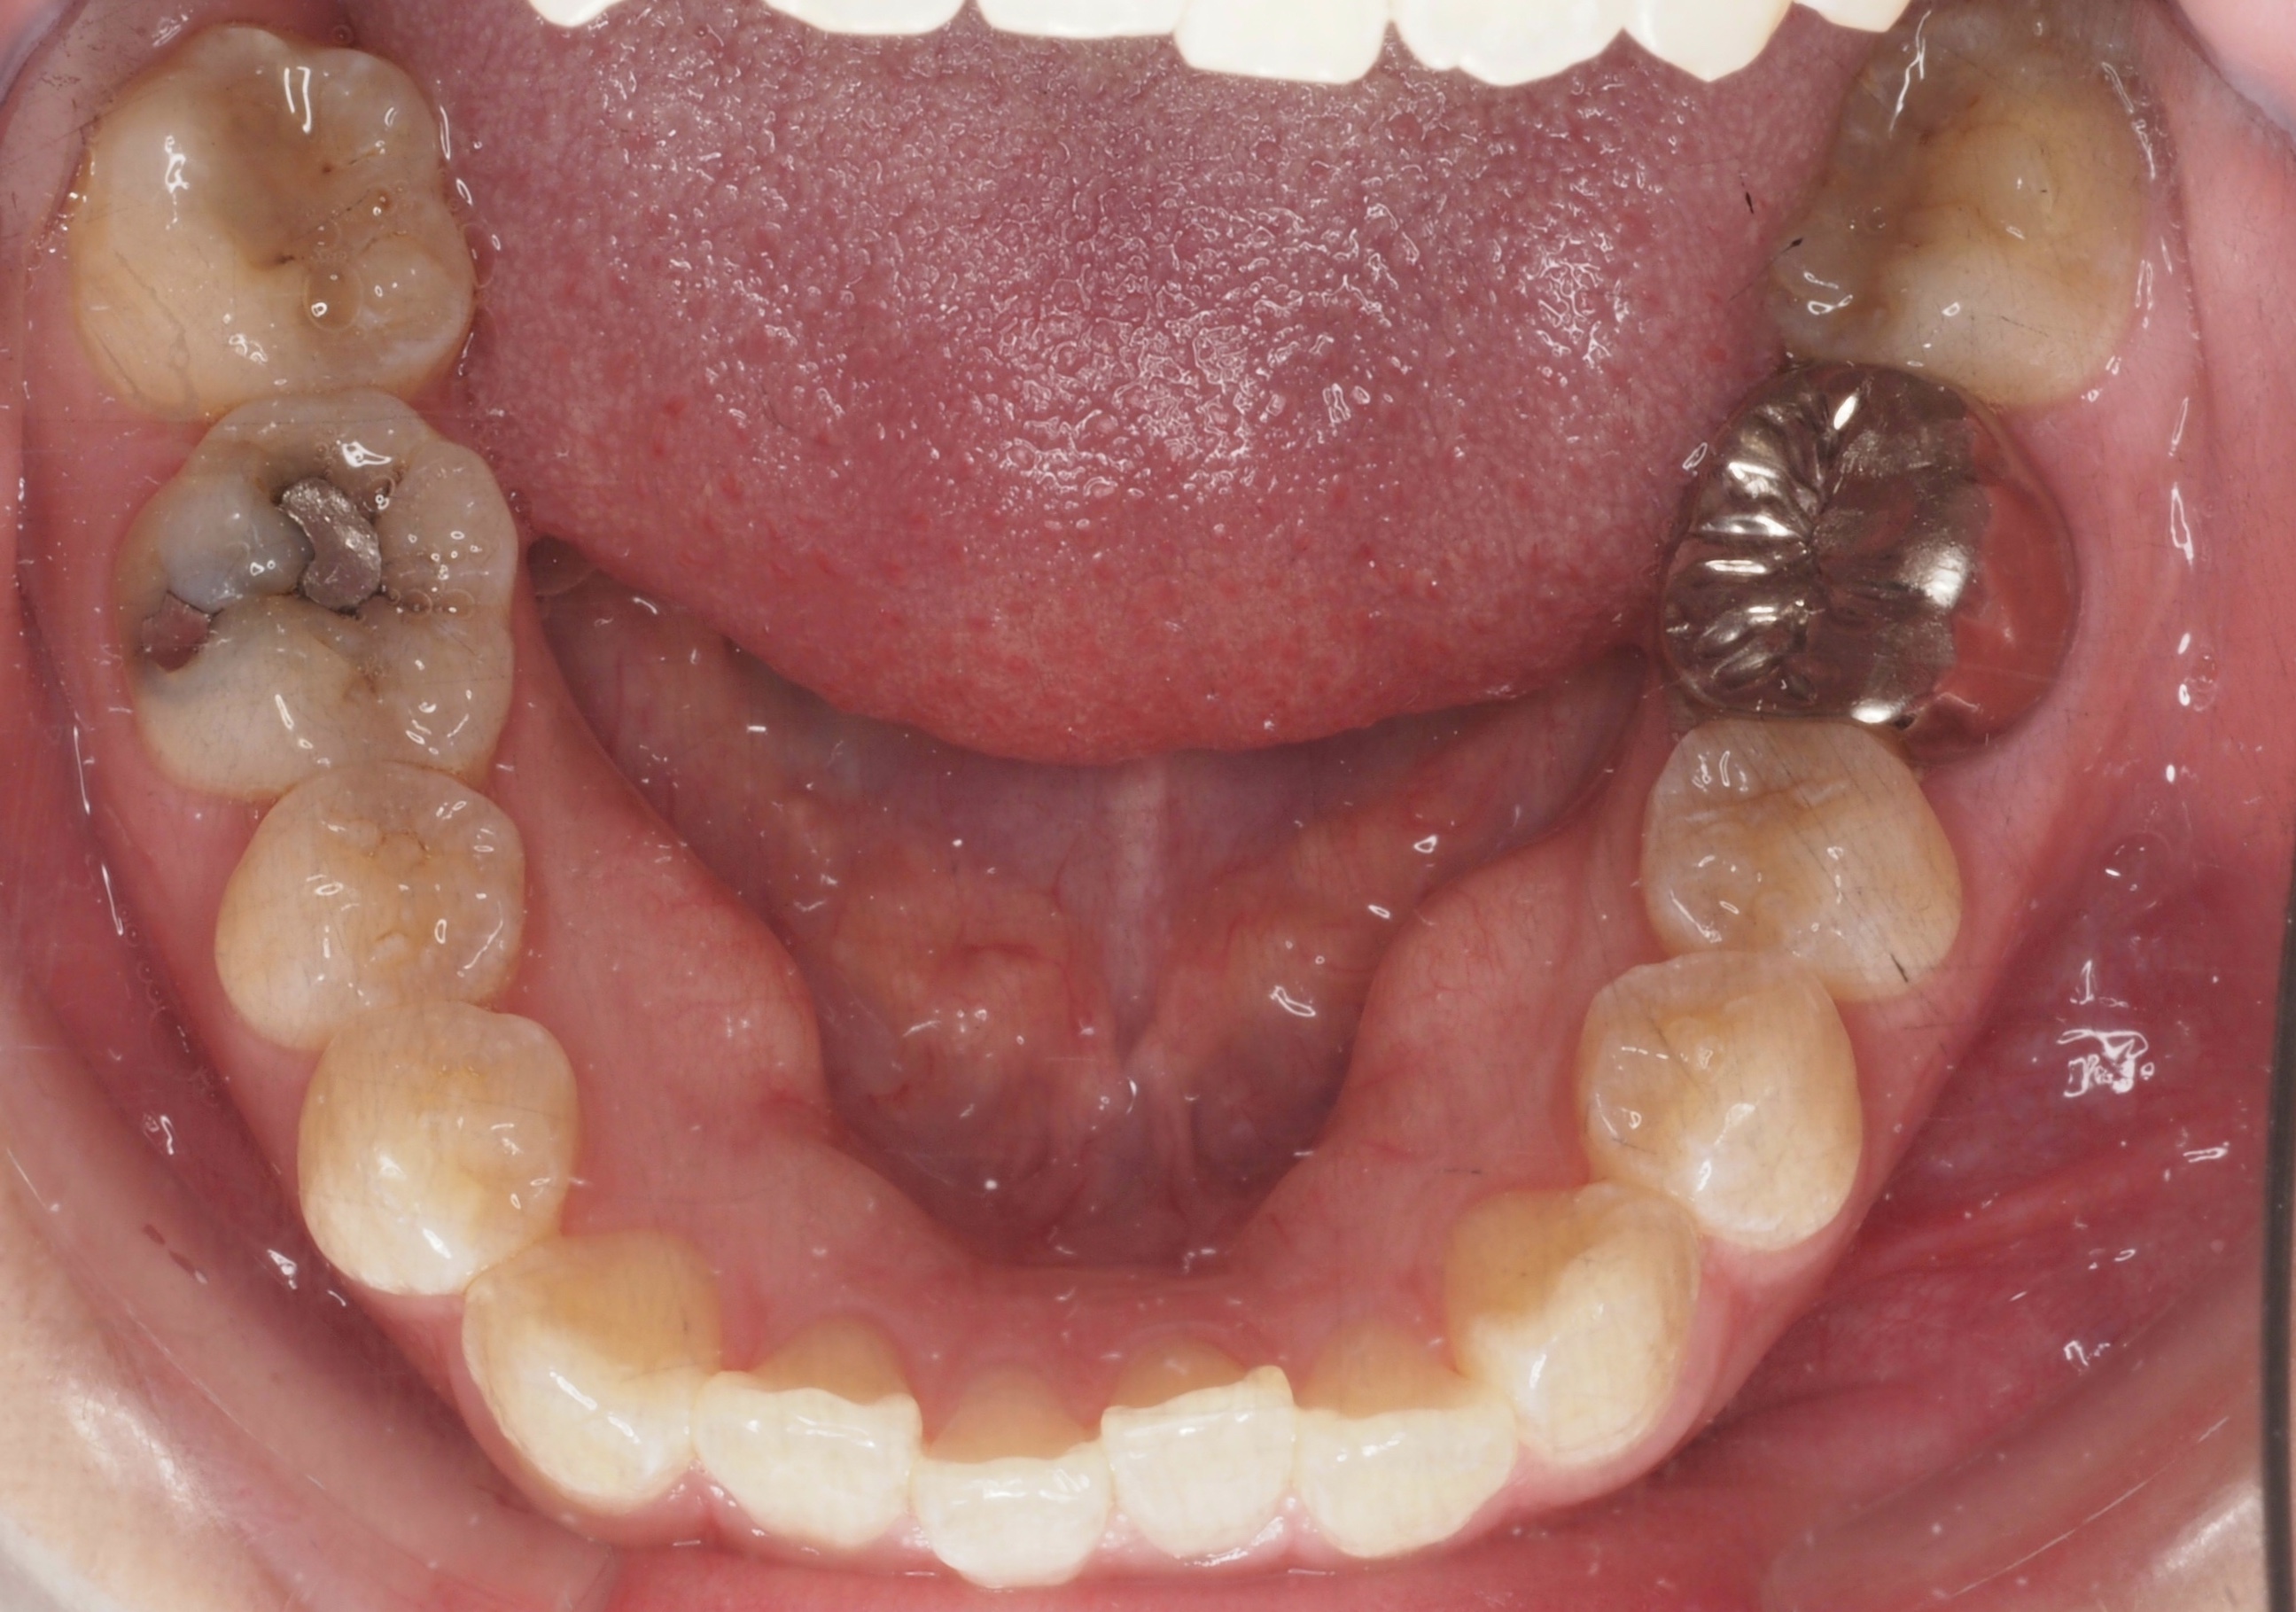

矯正スタート時(下顎)撮影:2018.07↓ 矯正7ヶ月経過(下顎)撮影:2019.04↓

下顎はきれいに並んできたと思います😁